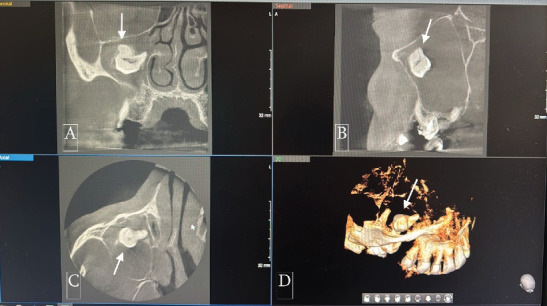

恒磨牙异位萌出是一种罕见的发育异常,其特征是牙位异常,可导致严重的并发症。在罕见的情况下,异位磨牙可能与含牙囊肿有关,特别是在上颌窦内,对诊断和治疗提出了挑战。本文报告一位58岁男性病患,表现为慢性右上颌鼻窦炎、间歇性面部疼痛及脓性鼻及口腔分泌物。放射学评估,包括锥束计算机断层扫描(CBCT),显示一个完全不透明的右上颌窦包含一个异位上颌磨牙。此外,发现一个与含牙囊肿一致的大囊性病变,占据整个窦腔。手术在全麻下采用Caldwell-Luc入路。这包括在上颌前壁制造一个骨窗,以方便切除异位牙和相关的囊性病变。组织病理学检查证实有牙性囊肿,表现为慢性炎症浸润和纤维化。上颌窦的异位磨牙通常无症状,但可表现为反复的鼻窦炎、疼痛和口窦沟通。存在一个大的含牙囊肿增加并发症的风险,并可能模糊放射学解释由于窦混浊。该病例强调了综合影像学检查和早期手术干预的必要性,以防止长期并发症。意识到这种罕见的情况可以帮助临床医生及时诊断和适当的管理,最终保留鼻窦功能,并尽量减少进一步的问题。

Ectopic eruption of permanent molars is an uncommon developmental anomaly characterized by abnormal tooth positioning, which can lead to significant complications. In rare instances, ectopic molars may be associated with dentigerous cysts, particularly within the maxillary sinus, posing challenges for diagnosis and management. This report discusses a rare case of a 58-year-old male who presented with chronic right maxillary sinusitis, intermittent facial pain, and purulent nasal and oral discharge. Radiological evaluation, including cone beam computed tomography (CBCT), revealed a completely opacified right maxillary sinus containing an ectopic maxillary molar. Additionally, a large cystic lesion consistent with a dentigerous cyst was found, occupying the entire sinus cavity. Surgical management was performed using the Caldwell-Luc approach under general anesthesia. This involved creating a bone window in the anterior maxillary wall to facilitate the removal of the ectopic tooth and the associated cystic lesion. Histopathological examination confirmed the presence of a dentigerous cyst exhibiting chronic inflammatory infiltration and fibrosis. Ectopic molars in the maxillary sinus are often asymptomatic but can present with recurrent sinusitis, pain, and oroantral communication. The existence of a large dentigerous cyst heightens the risk of complications and may obscure radiological interpretation due to sinus opacification. This case highlights the necessity of comprehensive imaging and early surgical intervention to prevent long-term complications. Awareness of such rare conditions can help clinicians in prompt diagnosis and appropriate management, ultimately preserving sinus function and minimizing further issues.